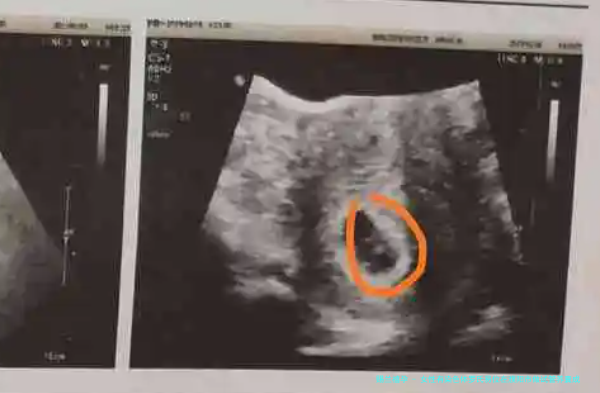

- 女的一方:血液常规、激素水平检查、染色体剖析、超声波检查等。